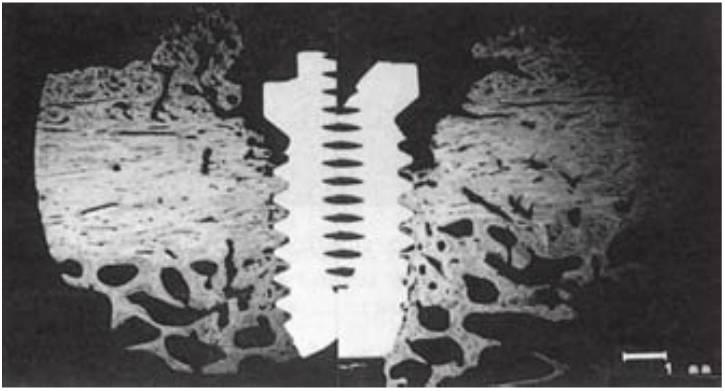

Al aplicar las fuerzas funcionales sobre el implante, el hueso a su alrededor es capaz de adaptarse al estrés y de aumentar su densidad, especialmente en la mitad crestal del cuerpo del implante desde el 6° mes hasta el año después de la carga del implante. En un estudio histológico e histomorfométrico del hueso, Piatelli y cols, observaron reacciones en monos con implantes cargados y no cargados (figs. 4-26 y 4-27). El hueso cambió de un patrón fino trabeculado después de la cicatrización inicial a un patrón trabecular más denso y grueso después de la carga, especialmente en la mitad crestal de la interfase del implante. Hoshaw cargó implantes insertados en perros con una carga tensional y observó que el patrón de hueso fino trabecular se transformó en hueso trabecular grueso alrededor del implante. Además, el hueso se reorganizó en una condición más favorable para resistir la dirección y el tipo de la carga oclusal (fig. 4-28).